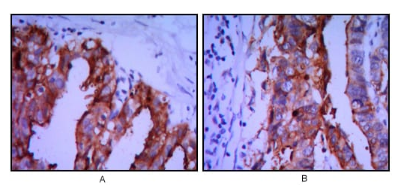

ALPP Mouse Monoclonal antibody[3E5C7]

IHC    1/200 - 1/1000